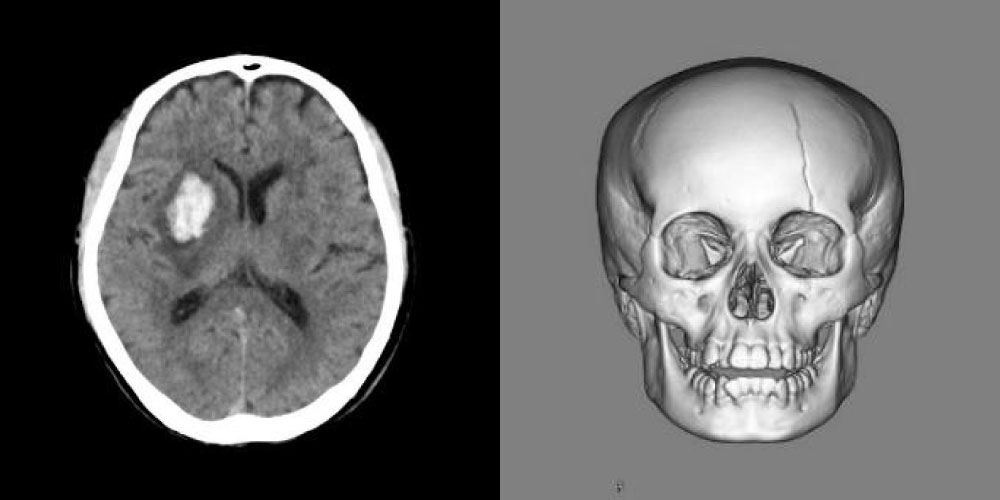

頭部領域

頭部CT検査は、頭の中の淡い病気の変化を鮮明に写し出すことが可能です。

脳内の出血や交通事故などによる骨折の状態を素早く、詳細に調べることが可能です。